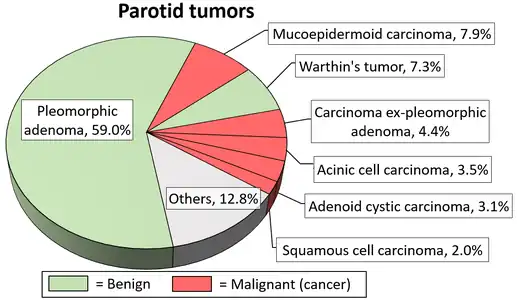

Pleomorphic adenoma (or benign mixed tumor) is a common benign salivary gland neoplasm characterised by neoplastic proliferation of epithelial (ductal) cells along with myoepithelial components, having a malignant potentiality. It is the most common type of salivary gland tumor and the most common tumor of the parotid gland. It derives its name from the architectural Pleomorphism (variable appearance) seen by light microscopy. It is also known as "Mixed tumor, salivary gland type", which refers to its dual origin from epithelial and myoepithelial elements as opposed to its pleomorphic appearance.

Diagrams by Mikael Häggström, MD - 1 2 3 4 5 Psychogios G, Bohr C, Constantinidis J, Canis M, Vander Poorten V, Plzak J, et al. (January 2021). "Review of surgical techniques and guide for decision making in the treatment of benign parotid tumors" (PDF). European Archives of Oto-Rhino-Laryngology. 278 (1): 15–29. doi:10.1007/s00405-020-06250-x. PMID 32749609. S2CID 220965351.